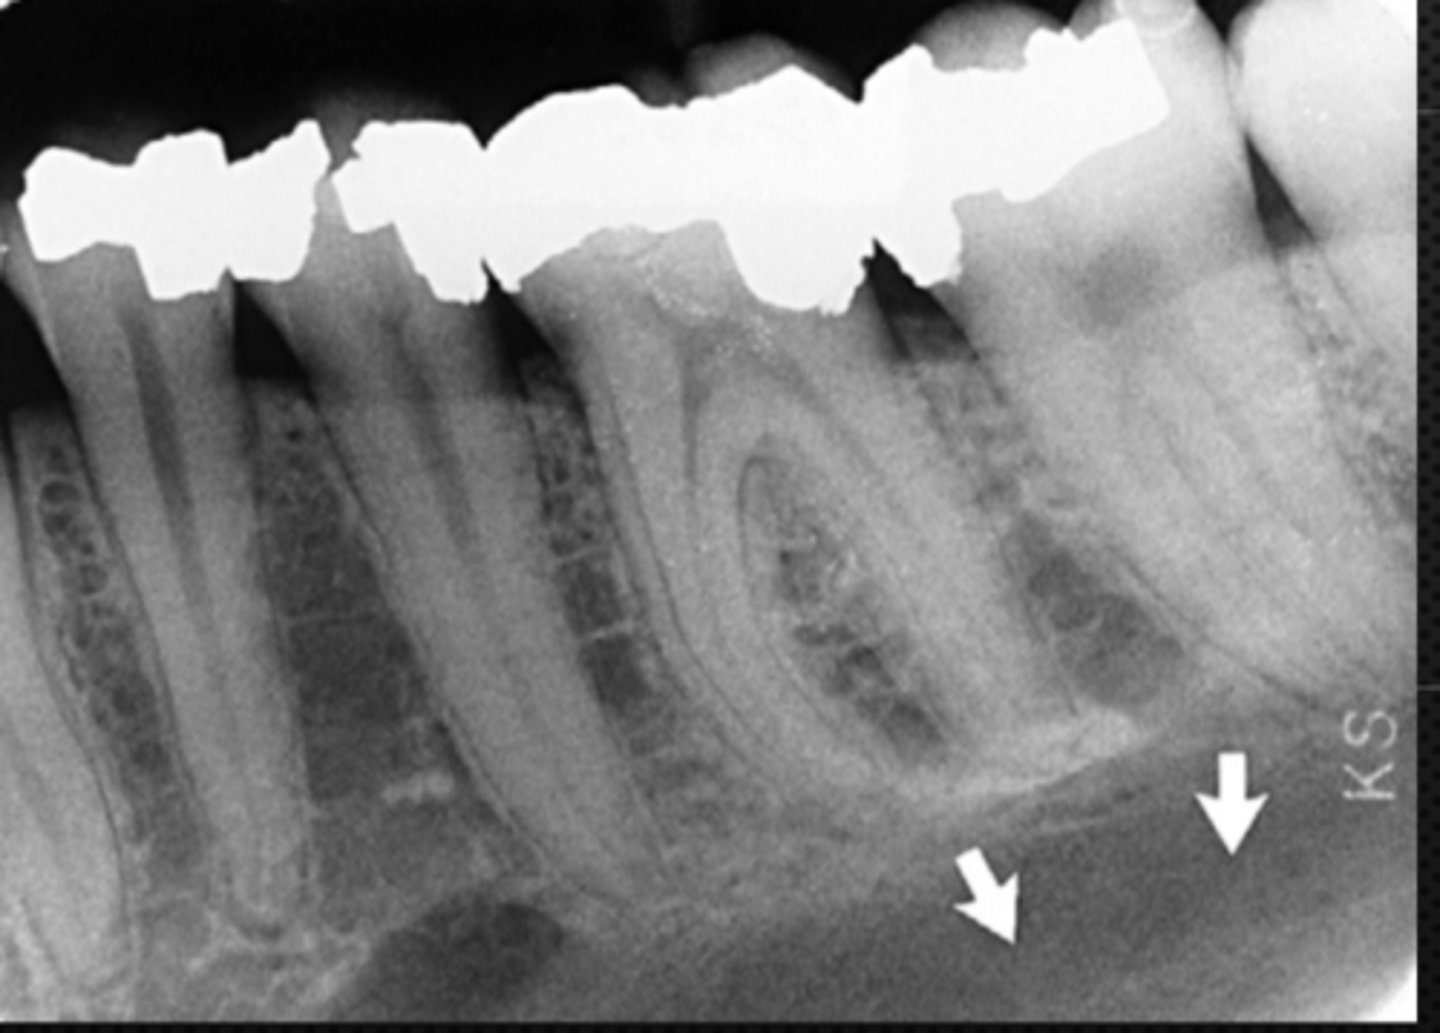

28

New cards

Mandibular canal

Identify the structure

<p>Identify the structure</p>

29

Identify the radiolucent structure

<p>Identify the radiolucent structure</p>

30

Nutrient canals (neurovascular canals)